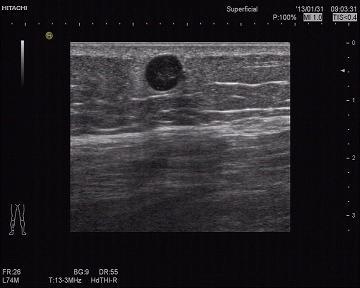

超声所见:右小腿肿物处皮下脂肪浅层可探及一0.7*0.73㎝低-无回声结节,边界清,CDI:其内充满血流信号,可见动脉频谱,并可见其右侧有一支动脉进入,检查过程中血流信号逐渐消失,此时患者自觉局部疼痛,观察5分钟后血流信号逐步恢复丰富状态。

超声提示:右小腿脂肪浅层结节—血管球瘤可能。病理结果为(右小腿)平滑肌瘤。